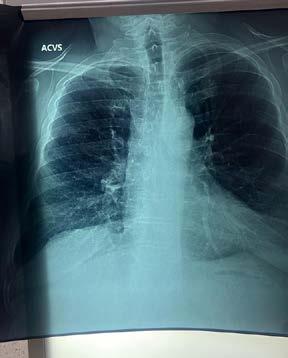

En el marco del Día Mundial de la Enfermedad Pulmonar Obstructiva Crónica (EPOC), que se conmemora el tercer miércoles de noviembre, el Instituto de Seguridad y Servicios Sociales de los Trabajadores del Estado (ISSSTE), a cargo del director general Martí Batres Guadarrama, llama a la población a evitar el consumo de tabaco con el propósito de prevenir el desarrollo de esta enfermedad.

El médico especialista en neumología de la Clínica de Especialidades (CE) “Indianilla”, Jorge López de la Cruz, explicó que la EPOC es una enfermedad patológica que se caracteriza por reducir el flujo de aire y atacar principalmente a los bronquios, lo cual deriva en múltiples problemas respiratorios.

“Las consecuencias a nivel fisiológico son, en principio, la inflamación y obstrucción de los bronquios. En algunos pacientes puede llegar a producir enfisema pulmonar, es decir, la destrucción de las paredes de los alvéolos (pequeños sacos de aire en los pulmones) que provocan que los pulmones dejen de cumplir con su función principal: tomar oxígeno del aire para que llegue a

la sangre y eliminar el dióxido de carbono del cuerpo”, detalló.

López de la Cruz indicó que, a pesar de que existen múltiples factores de riesgo que pueden provocar la EPOC, como la exposición al humo de leña “principalmente en comunidades rurales”, la contaminación del ambiente, secuelas de tuberculosis, asma mal tratado o alguna alteración a nivel genético, la principal causa es el tabaquismo.